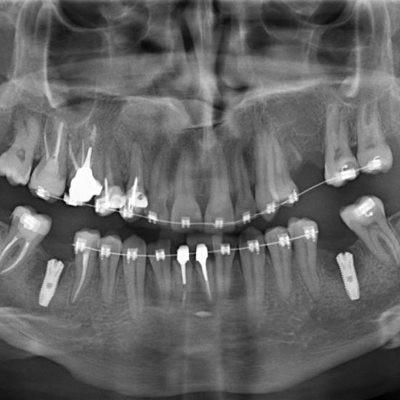

Такое исследование позволяет определить проблемы не только 2−3 соседних зубов, но и диагностировать состояние всей зубочелюстной системы и прилегающих структур, выявить на ранней стадии кисты, гранулемы, опухоли. Благодаря возможностям панорамного снимка удается более четко определить пораженный зуб, обнаружить различные аномалии развития, уточнить оптимальное место для вживления импланта, максимально качественным образом провести ортодонтическое и пародонтологическое лечение.

Несмотря на то, что прицельный снимок зубов по-прежнему широко используется в стоматологии, все более значимую роль играют и другие виды диагностики. Чтобы добиться максимально качественного результата лечения зубов, специалисты клиники Совершенная улыбка активно обращаются к ортопантомограмме

Панорамный снимок становится все более востребованным в качестве скрининговой методики. Высокая скорость проведения исследования, использование современного оборудования позволяют считать такой вид диагностики абсолютно безопасным. Она может проводиться по мере необходимости, несколько раз в году.